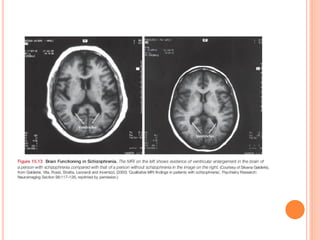

1.       Brain structure

     Prefrontal cortex is smaller and shows less activity

     Enlarged ventricles (cavities inside the brain

containing cerebrospinal fluid).